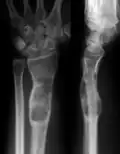

X-ray showing enchondromas localized in the lower part of the radius of a 37-year-old patient affected with Ollier disease